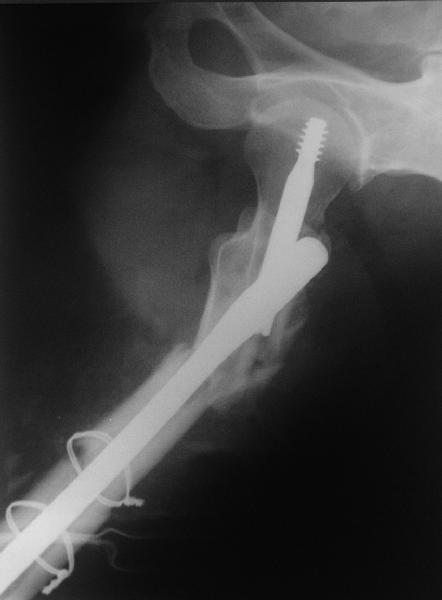

В общем, сделали. См. приложение.

Длина и из-за этого ось получились не совсем такие, как хотелось бы, все-таки срок после той операции уже 6 недель. Может быть, стоило провести дистракцию аппаратом неделю-другую. Заранее спасибо за комментарии и критику.

Александр, поздравляю от души, отличная работа, вообще-то и у меня тоже были опасения по поводу латеральной стенки. Идеальное показаниt к применению импланта закрытым методом при таких переломах, когда болт замыкается в штифте, конструкции придается угловая жесткость, примерно как в Blade Plate.

При отсутствии таких конструкций, другим альтернативным методом фиксации можно было рекомендовать короткий DHS с двумя шурупами открытым методом, а в диафиз ретроградний штифт.